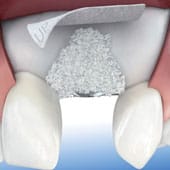

Colocación Quirúrgica del Implante

La colocación del implante se realiza bajo anestesia local, como si fuera una obturación. Es un procedimiento indoloro, que junto con la medicación prescrita hará que el paciente tenga un postoperatorio sin apenas molestias.

Oseointegración y Curación del Implante

Una vez colocado el implante se deberá esperar un tiempo, para que el propio hueso del paciente crezca alrededor del implante, gracias a un proceso biológico llamado osteointegración descrito hace ya más de 50 años por el profesor Branemark, el implante se sujeta al hueso. Una vez formada dicha integración es cuando el implante puede soportar la nueva prótesis o diente artificial.